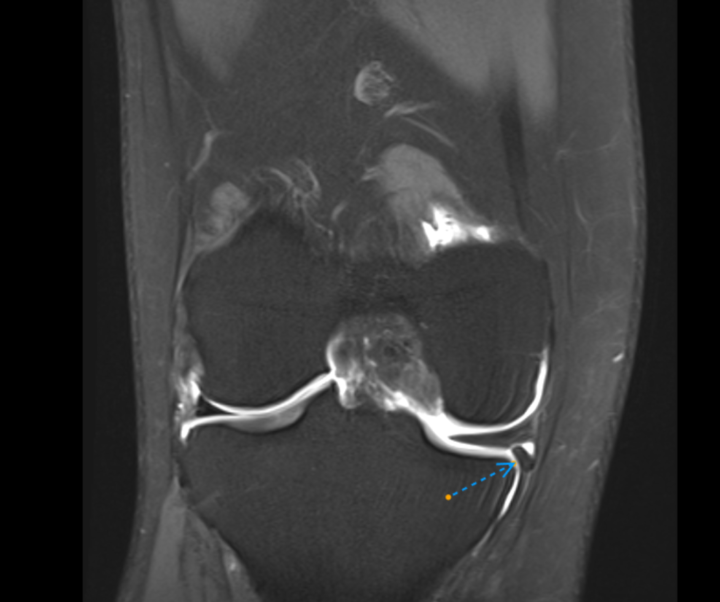

Knee MR arthrography.

Male 26 yo. Car crash 7 y ago. Prior simple MRI - partial ACL tear (hight grade). No medial meniscus pathology. I see this fragment inferior to medial meniscus, but not sure if its fragment or smth else. Any insights? Case at cmrad --> https://www.cmrad.com/cases/1779861922